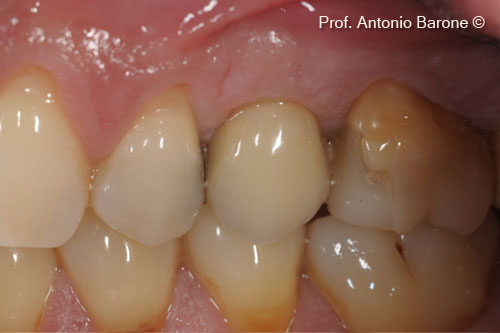

Hình ảnh nhìn từ phía má 3 năm sau khi cấy ghép implant

Hình ảnh lâm sàng mặt ngoài má 5 năm sau khi cấy ghép implant

Hình ảnh lâm sàng mặt ngoài má 7 năm sau khi cấy ghép implant